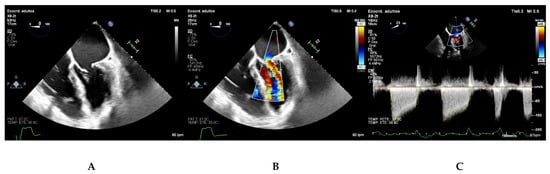

5.1. Parasternal Long-Axis View

5.2. Parasternal Short-Axis View

5.3. Apical Four Chamber View